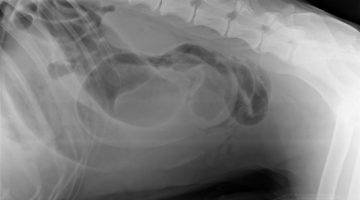

Veterinarska mafija u Hrvatskoj – mafija u hrvatskoj veterini. Veterinarska ambulanta Lonjica – Veterinarska stanica Vrbovec prikriva istinu o stručnoj pogrešci na mom psu. Napravili stručnu pogrešku, lžirali i krivotvorili nalaze, a u sve je upletena i Hrvatska veterinarska komora i predsjednik Visokog časnog suda Hrvatske veterinarske komore.